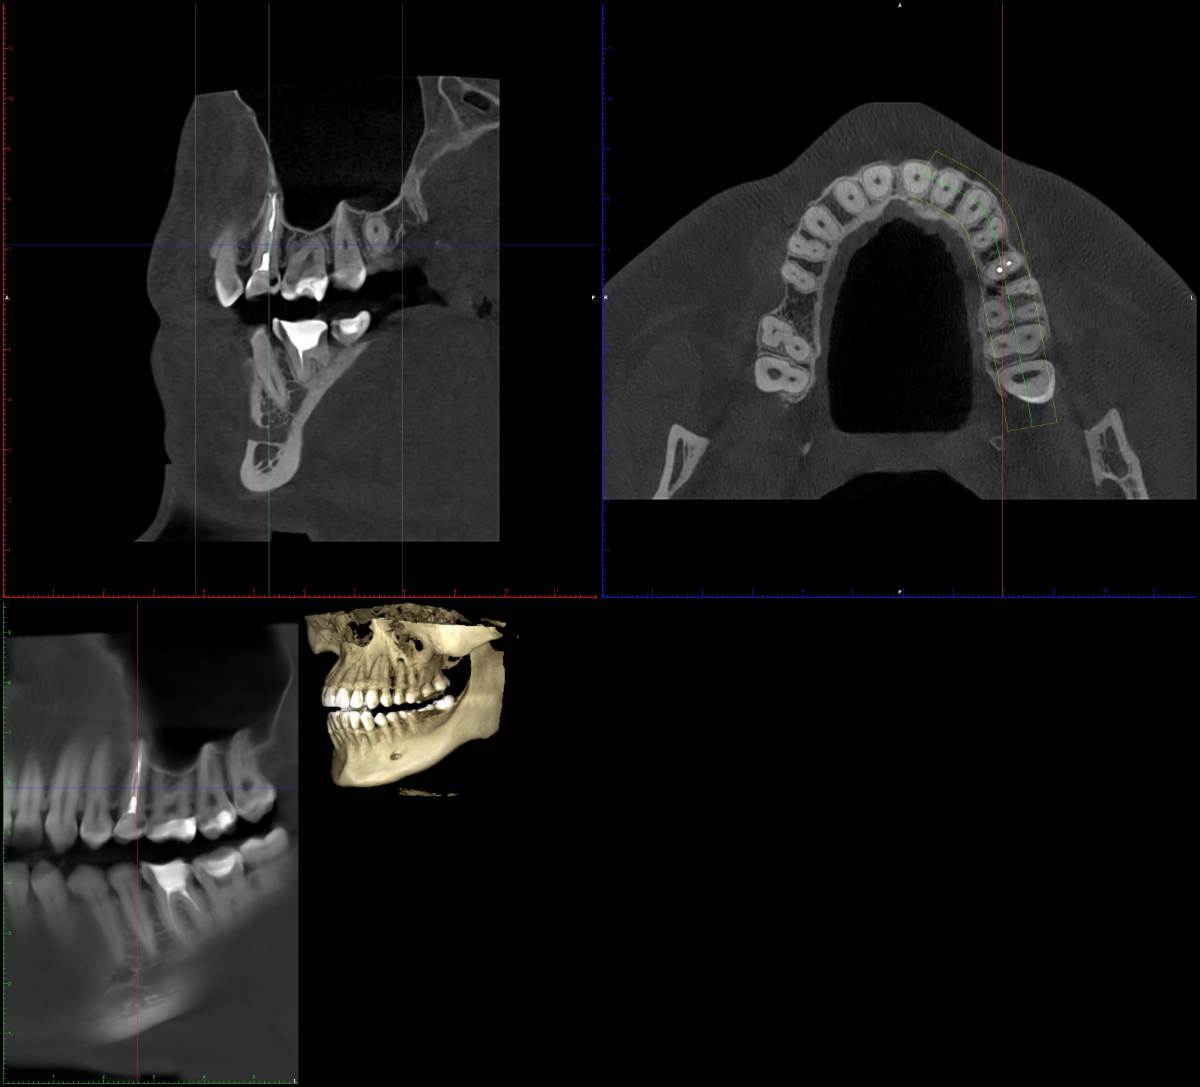

Л93 Опубликовано Понедельник в 18:57 Поделиться Опубликовано Понедельник в 18:57 (изменено) Доброго времени суток. Очень нужна консультация. В субботу припухла щека, заболела верхняя челюсть, конкретное место определить не удалось. Сегодня на осмотре у стоматолога вердикт, удалять 8ку и 5ку. Пошла на удаление, хирург внимательно изучив снимки, посоветовавшись с коллегой сказал, что 5ка под лечение, 8ка ещё и не вышла и с ней все в порядке. Прописал антибиотик и отправил к терапевту. Ближайшая запись к терапевту май. Действительно ли можно обойтись без удалении 5ки? Как срочно нужно заняться лечением если возможно вылечить 5ку? Заранее спасибо всем ответившим. Изменено Понедельник в 18:59 пользователем Л93 Ссылка на комментарий

Женька Опубликовано Понедельник в 19:36 Поделиться Опубликовано Понедельник в 19:36 Здравствуйте! Криминала не вижу по Вашему 25 зубу. Но это лишь один срез, не дающий полной картины. По 8... интересно посмотреть в полости рта. Потому что на снимке 6 лет назад она действительно не прорезалась, а вот на свежем вполне себе должна жевать с нижней 8. Ссылка на комментарий

Л93 Опубликовано Вторник в 09:59 Автор Поделиться Опубликовано Вторник в 09:59 @red_butler вчерашний снимок кт в первом сообщении Ссылка на комментарий

wladdX Опубликовано Вторник в 21:40 Поделиться Опубликовано Вторник в 21:40 (изменено) Скорее всего виновен 25 Изменено Вторник в 21:41 пользователем wladdX Ссылка на комментарий

red_butler Опубликовано 16 часов назад Поделиться Опубликовано 16 часов назад Здравствуйте, требуется повторное лечение корневых каналов пятого зуба. почитайте эту тему Ссылка на комментарий